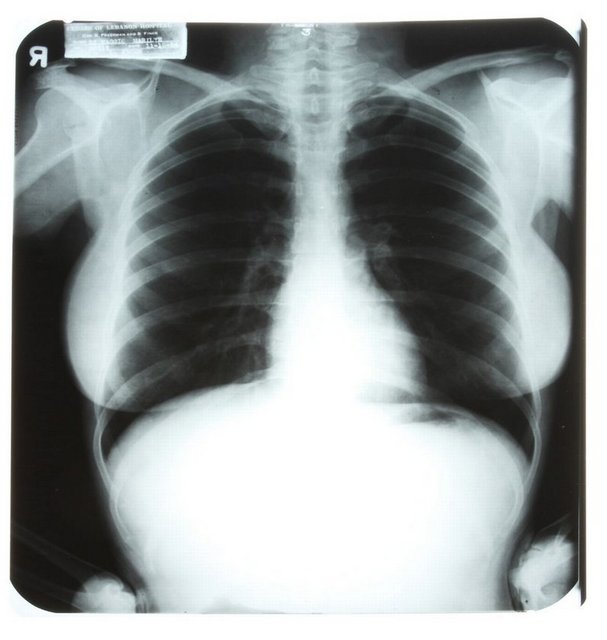

Sinemanın efsane sarışını Marilyn Monroe'nun geçirdiği estetik operasyonları belgeleyen röntgen filmleri ve doktorların birbirleriyle yazışmaları California'da yapılacak bir açık artırmada satışa sunuluyor